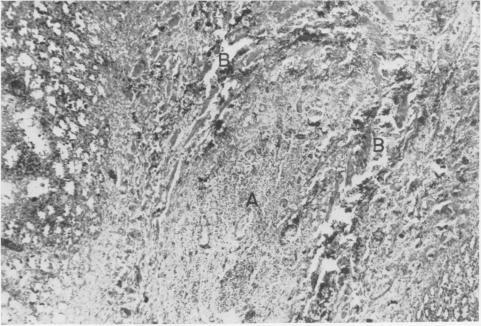

Experimental Pancreatitis A Possible Etiology of Postoperative Pancreatitis.

Ann Surg. 1962 Apr;155(4):523-31. doi: 10.1097/00000658-196204000-00007.